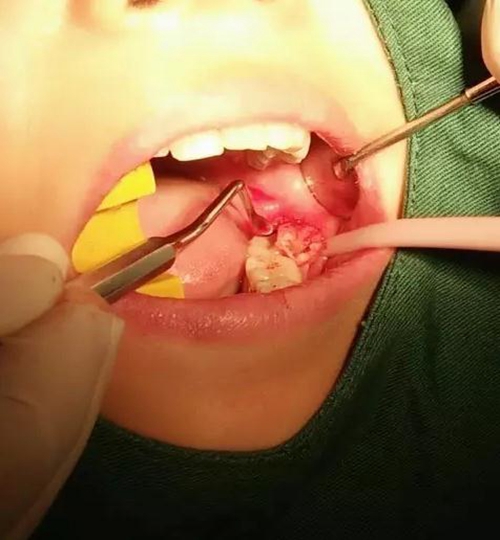

挖匙取出

術(shù)中拍片發(fā)現(xiàn),還有剩余,繼續(xù)。。。。